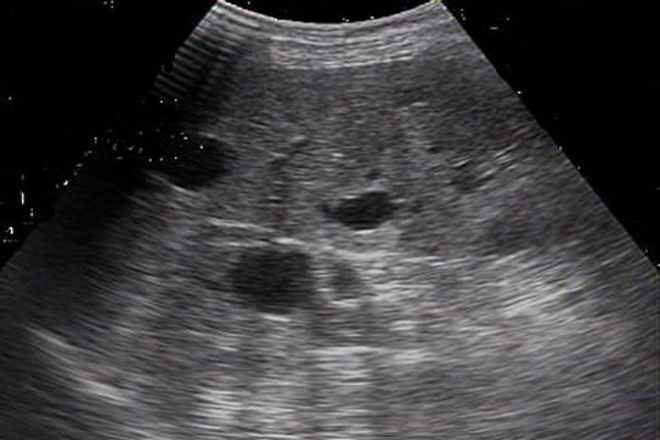

La enfermedad poliquística del hígado es la manifestación extrarrenal más frecuente de la enfermedad poliquística renal autosómica dominante y se asocia en 57%  de los casos a quistes en otros órganos como pulmón, páncreas,bazo y ovario, se requieren imágenes  diagnósticas complementarias para obtener la caracterización como la ecografía y la TAC que tienen como criterios diagnósticos los bordes finos con paredes bien redondeadas y sin imágenes en su interior.

Se trata de una paciente de 53 años con enfermedad de inicio incidioso  y tres años de evolución, caracterizada por dolor abdominal superior acompañado de  distensión pospandrial y síntomas de gastritis que al cabo de unos meses se  acompañó de crecimiento  del perímetro abdominal con palpación de masa por parte de la misma paciente lo que motivo a consultar al médico. Al realizar una TC se observaron múltiples quistes hepáticos y quistes renales sin alteración de la función renal.